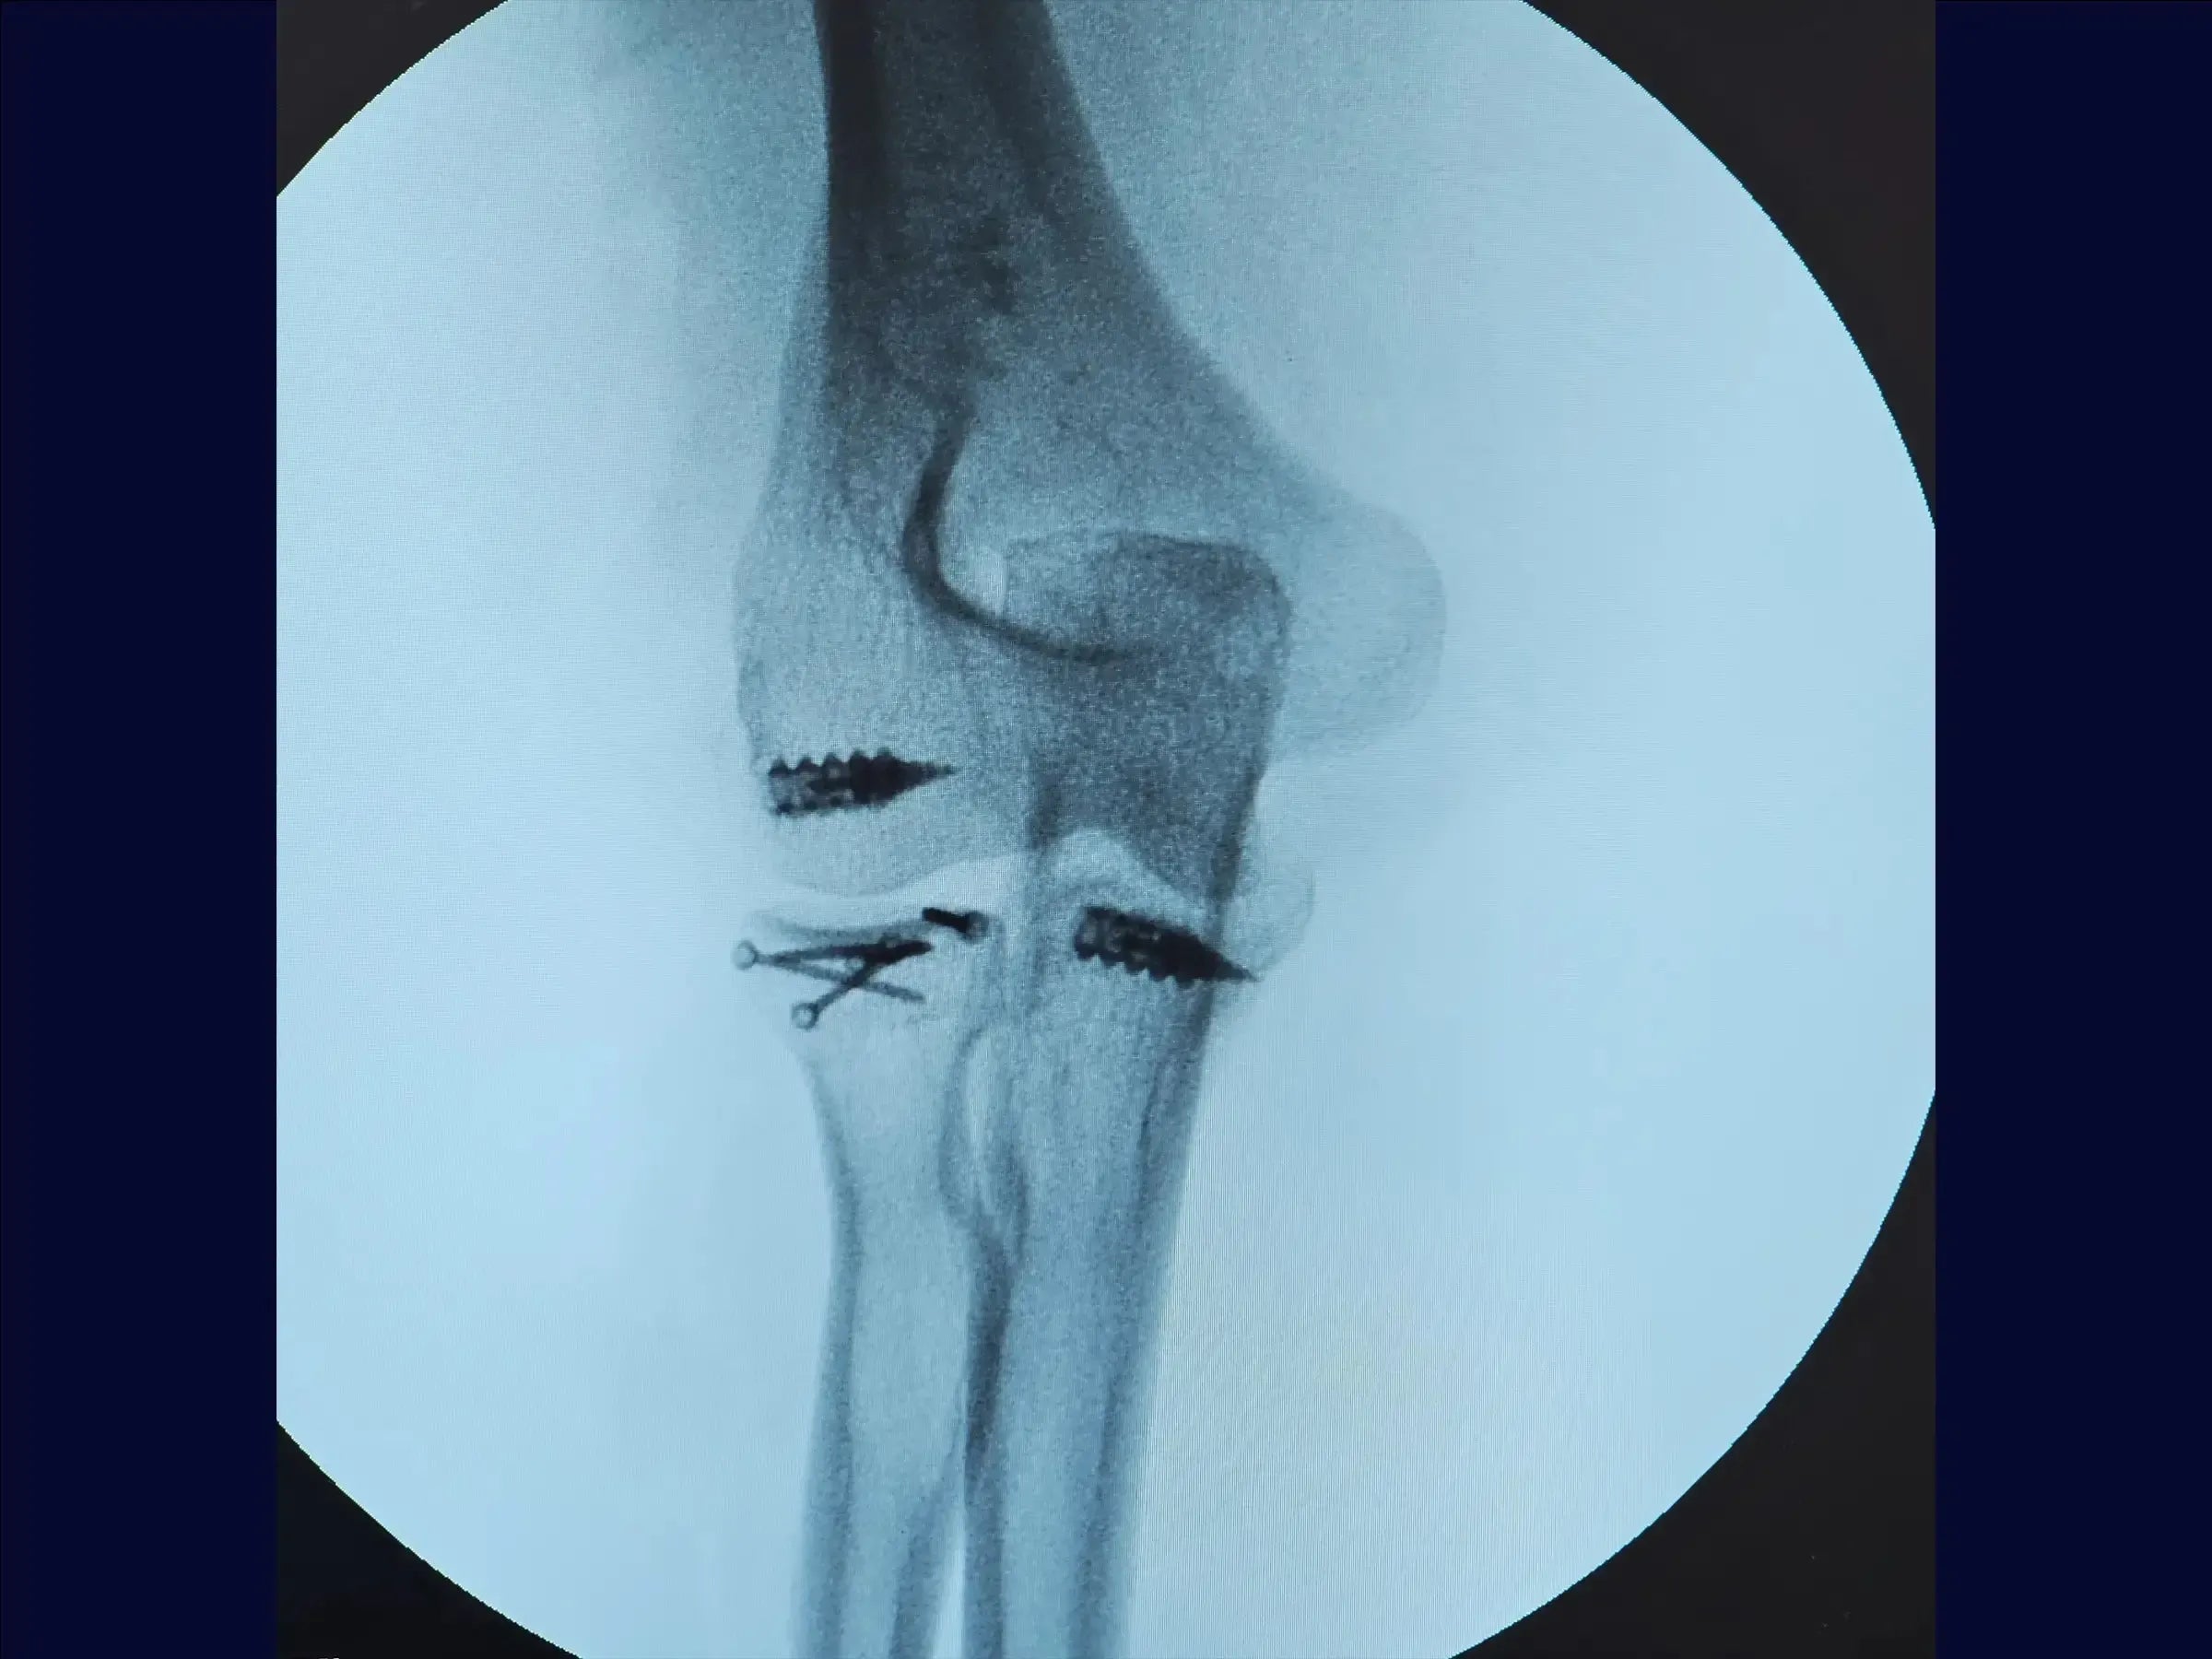

- Síntesis de cabeza radial Osteoss : utilizar tornillos de 1,5 mm, paralelos o divergentes, sin cruzar, para una fijación subcondral estable .

- Reparación del proceso coronoideo y la cápsula: utilice un ancla de metal de 5,0 mm y suturas de alta resistencia para suturar firmemente la cápsula articular anterior.

- Reparación del ligamento lateral: reinsertar el ligamento con ancla y ajustar con valgo para asegurar una tensión adecuada.

- Cierre y Prueba: Cerrar por planos y verificar el rango de movimiento intraoperatorio , asegurando la ausencia de bloqueos.

- Postoperatorio : Iniciar la movilidad temprana, excepto la extensión (limitada a 45° durante tres semanas). La estabilidad depende de la reducción anatómica, no solo de la fijación.